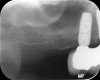

Fig 9. Tilted implant solutions for maxillary posterior partial edentulism. In the same manner that tilted implants can be used to

avoid the need for sinus grafting in full-arch implant prostheses, they can be used to avoid direct or indirect sinus grafting when insufficient posterior

maxillary bone volume challenges a fixed dental prosthesis implant restoration. Fig 7: Software planning for implant placement is shown with

tilting of the distal implant along the anterior wall of the maxillary sinus where there is insufficient bone in zone 3. Fig 8: Postoperative radiograph

of the implants and abutments reveals the angulation of the implant resolved by the CAD/CAM abutment. Fig 9: Final radiograph of the implant

prosthesis following restorations demonstrates the inclusion of a tooth in the molar position without sinus grafting.

Figure 9